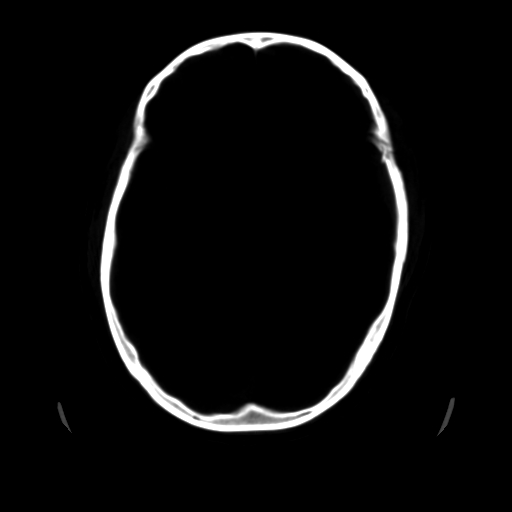

男,51岁,头外伤一小时,呕吐两次。

1)左侧中颅窝蝶骨翼后方硬膜外血肿。2)左侧颞顶部硬膜下血肿。3)蛛网膜下腔出血。4)左侧筛窦及双侧蝶窦炎症(或积血)。5)左侧额部头皮软组织肿胀。